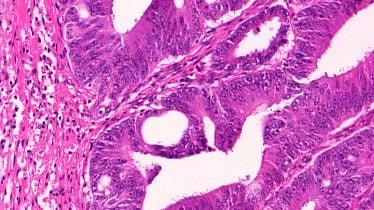

Early identification of Lynch Syndrome in a patient’s family members has the potential to reduce their cancer risk and mortality. Wikimedia Commons

Completed genetic testing would determine whether a patient had Lynch syndrome (LS), a hereditary marker for a higher-than-average predisposition for developing colorectal cancer as well as other cancers including endometrial and ovarian. Early identification of LS in a patient’s family members has the potential to reduce their cancer risk and mortality, increasing the medical benefit and thereby ultimately lowering testing costs, the study found.